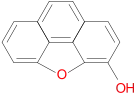

Oripavine derivatives

Thienorphine

Structures

| Oripavine derivatives | ||||

|---|---|---|---|---|